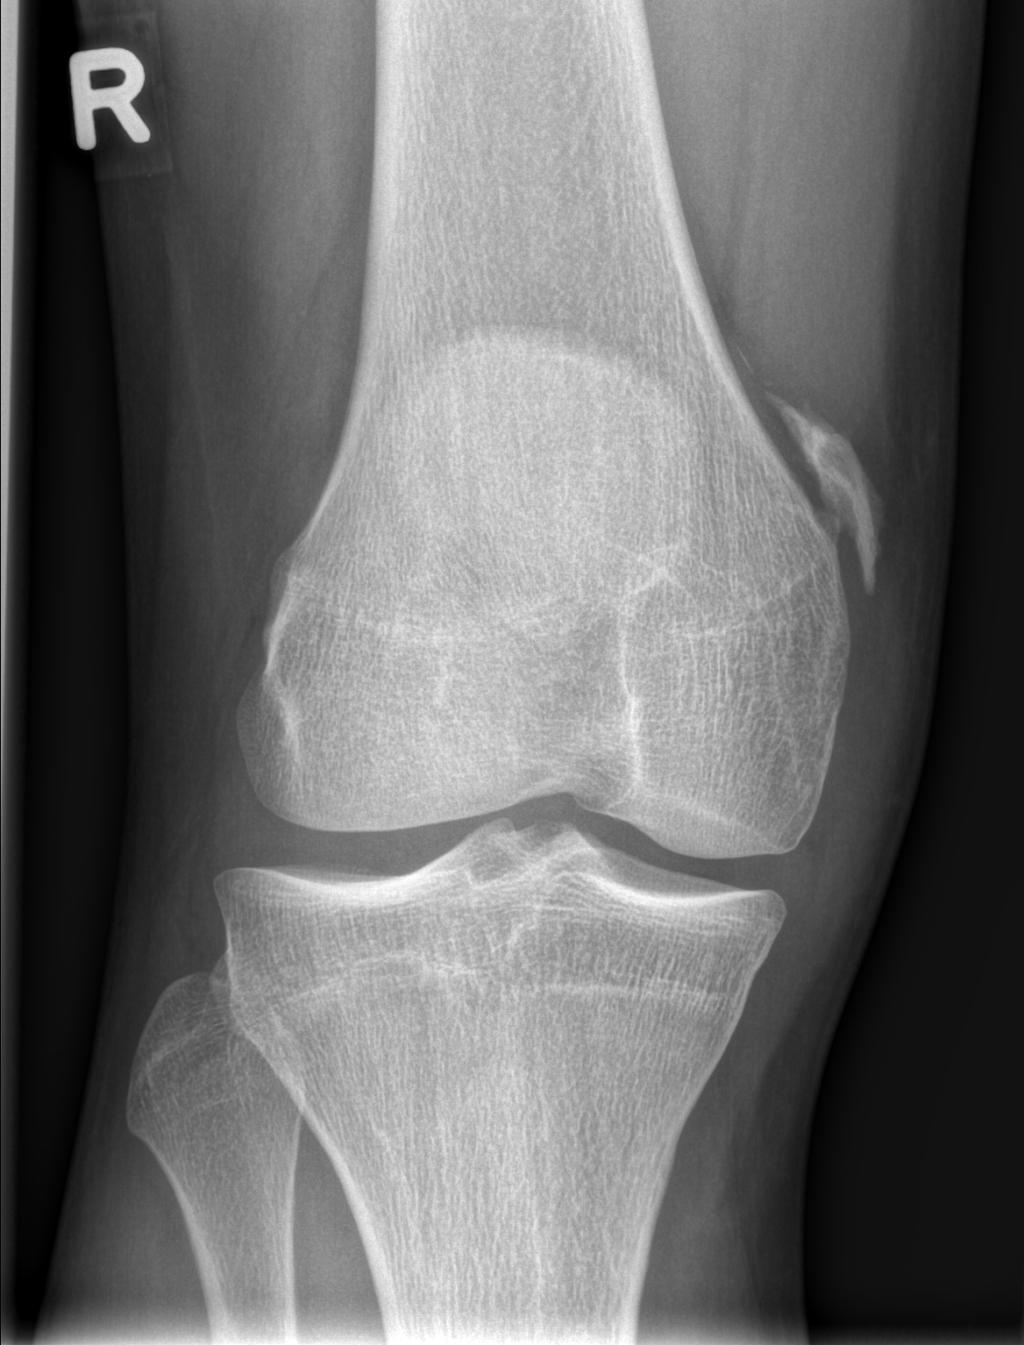

Een 19-jarige man bezocht de polikliniek Orthopedie vanwege pijn en een zwelling aan de mediale zijde van zijn rechter knie. Hij had 1,5 jaar eerder 2 maal een distorsie van de knie gehad tijdens het voetballen.

Wat is uw diagnose?